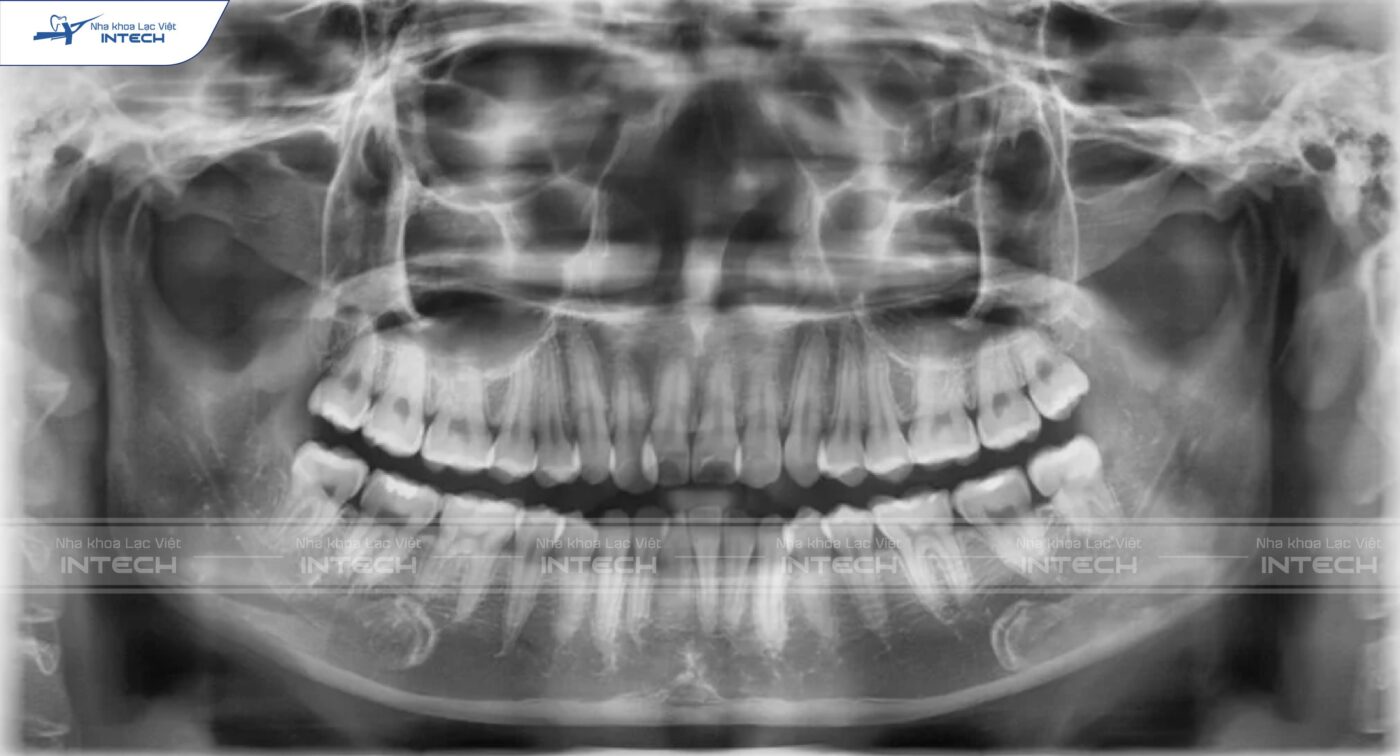

Phim toàn cảnh (Panorama):

Loại phim này giúp khảo sát toàn bộ răng trên cung hàm, số lượng, đặc điểm chân răng, răng ngầm, răng sữa, mầm răng vĩnh viễn, răng không,… Ngoài ra trên phim Panorama, bác sĩ cùng đánh giá được một số loại bệnh lý như sâu răng, viêm quanh cuống, viêm nha chu,…

Tất cả những vấn đề này đều góp phần giúp bác sĩ có một chẩn đoán đầy đủ và chính xác, không bị bỏ sót vấn đề.